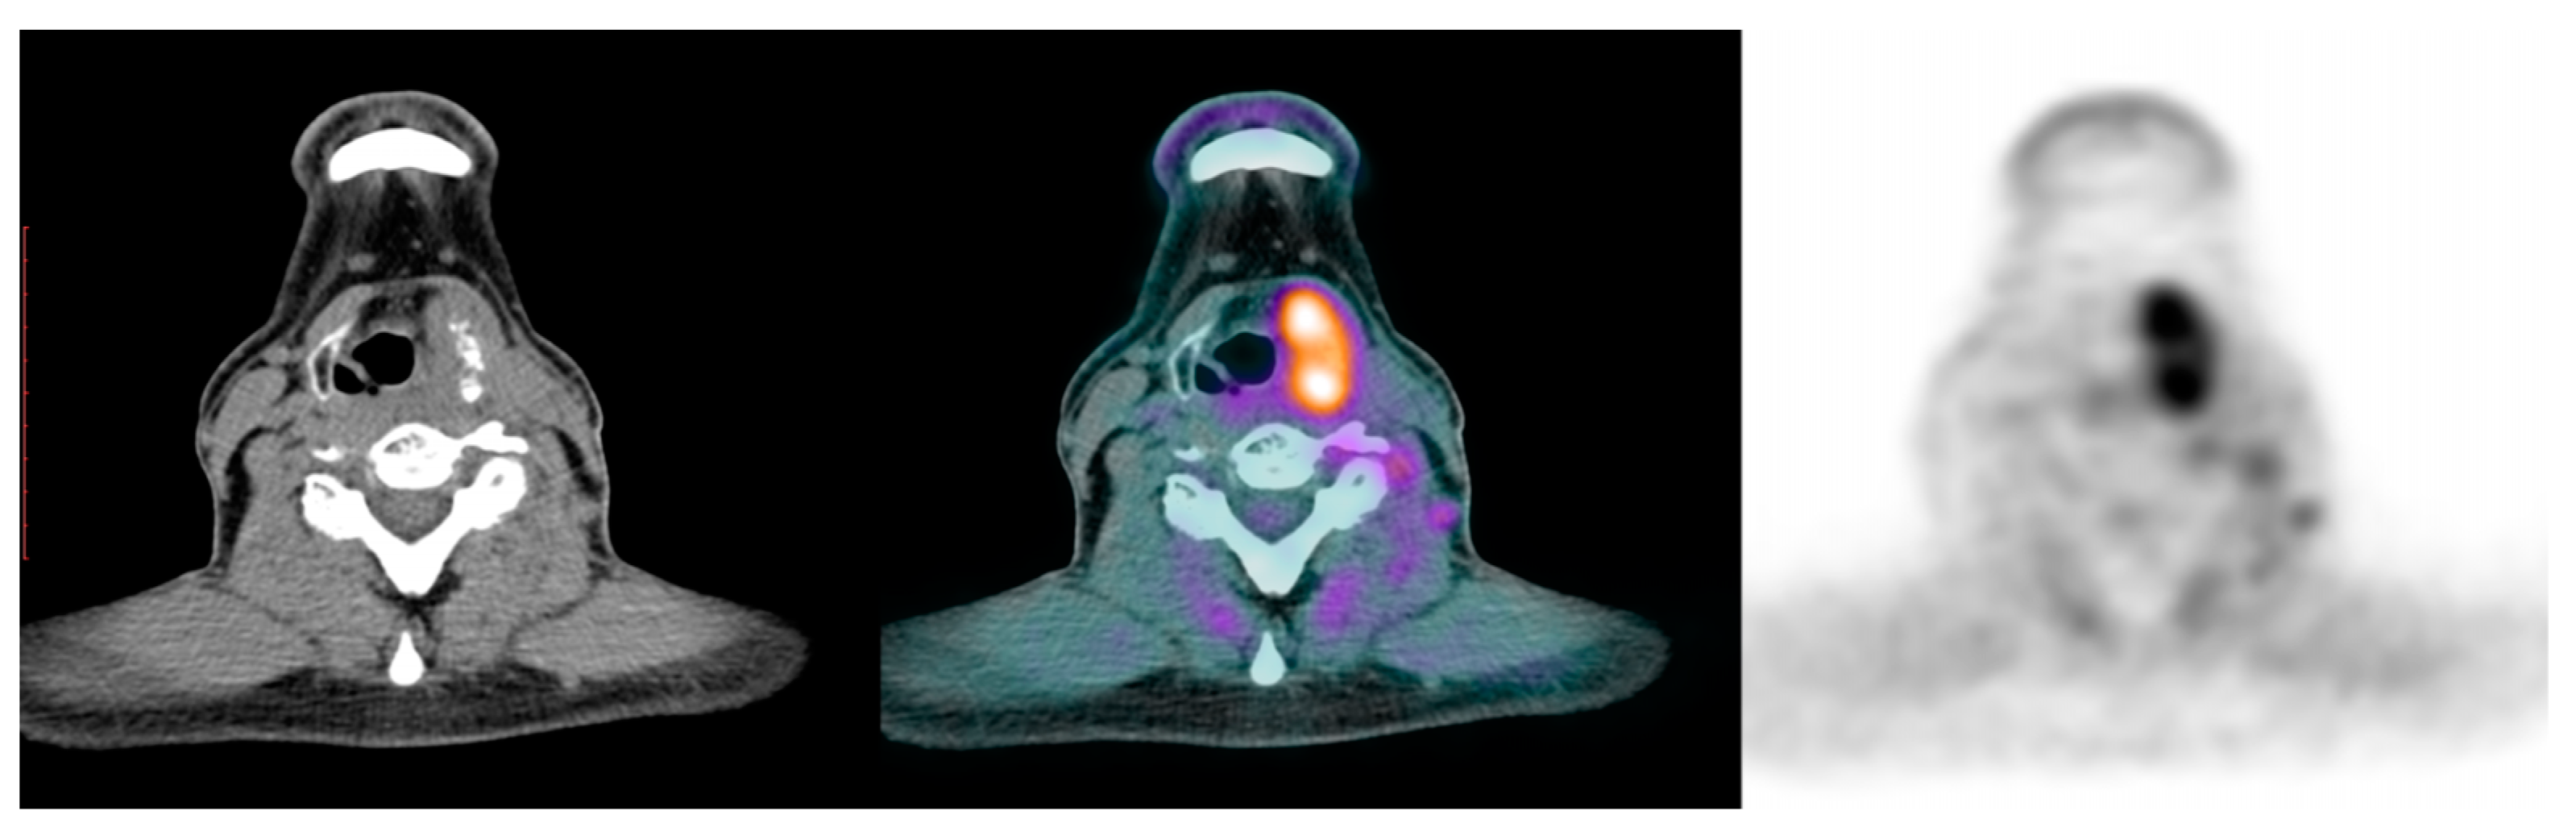

| PRESENT CASE | 1 | 1/0 | 45 | PDTC, hobnail, tall-cell | 1/1 | 1/1 (brain, bone, sinus) | 1/1 | TTmy (+neck dissection, completion ND) | 2 | Lenvatinib, sorafenib, trametinib/dabrafenib | DOD | BRAF |